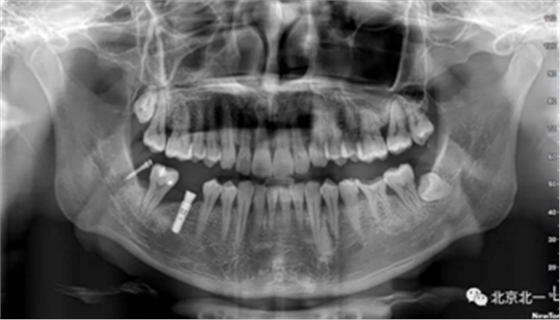

正畸支抗直立47

第一次支抗钉脱落, 第二次支抗钉位于48位置, 颊侧舌侧舌侧扣牵引。

直立后维持位置, 并取模戴牙。